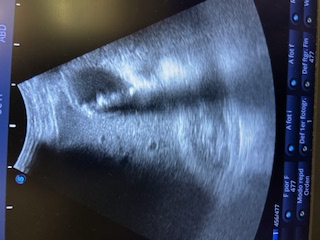

Ecografía: Distensión vesicular con numerosas litiasis intravesicales con pared engrosada de unos 8,74 mm. Ademas, línea hipoecoica en la pared con edema perilesional en área contigua al hígado.